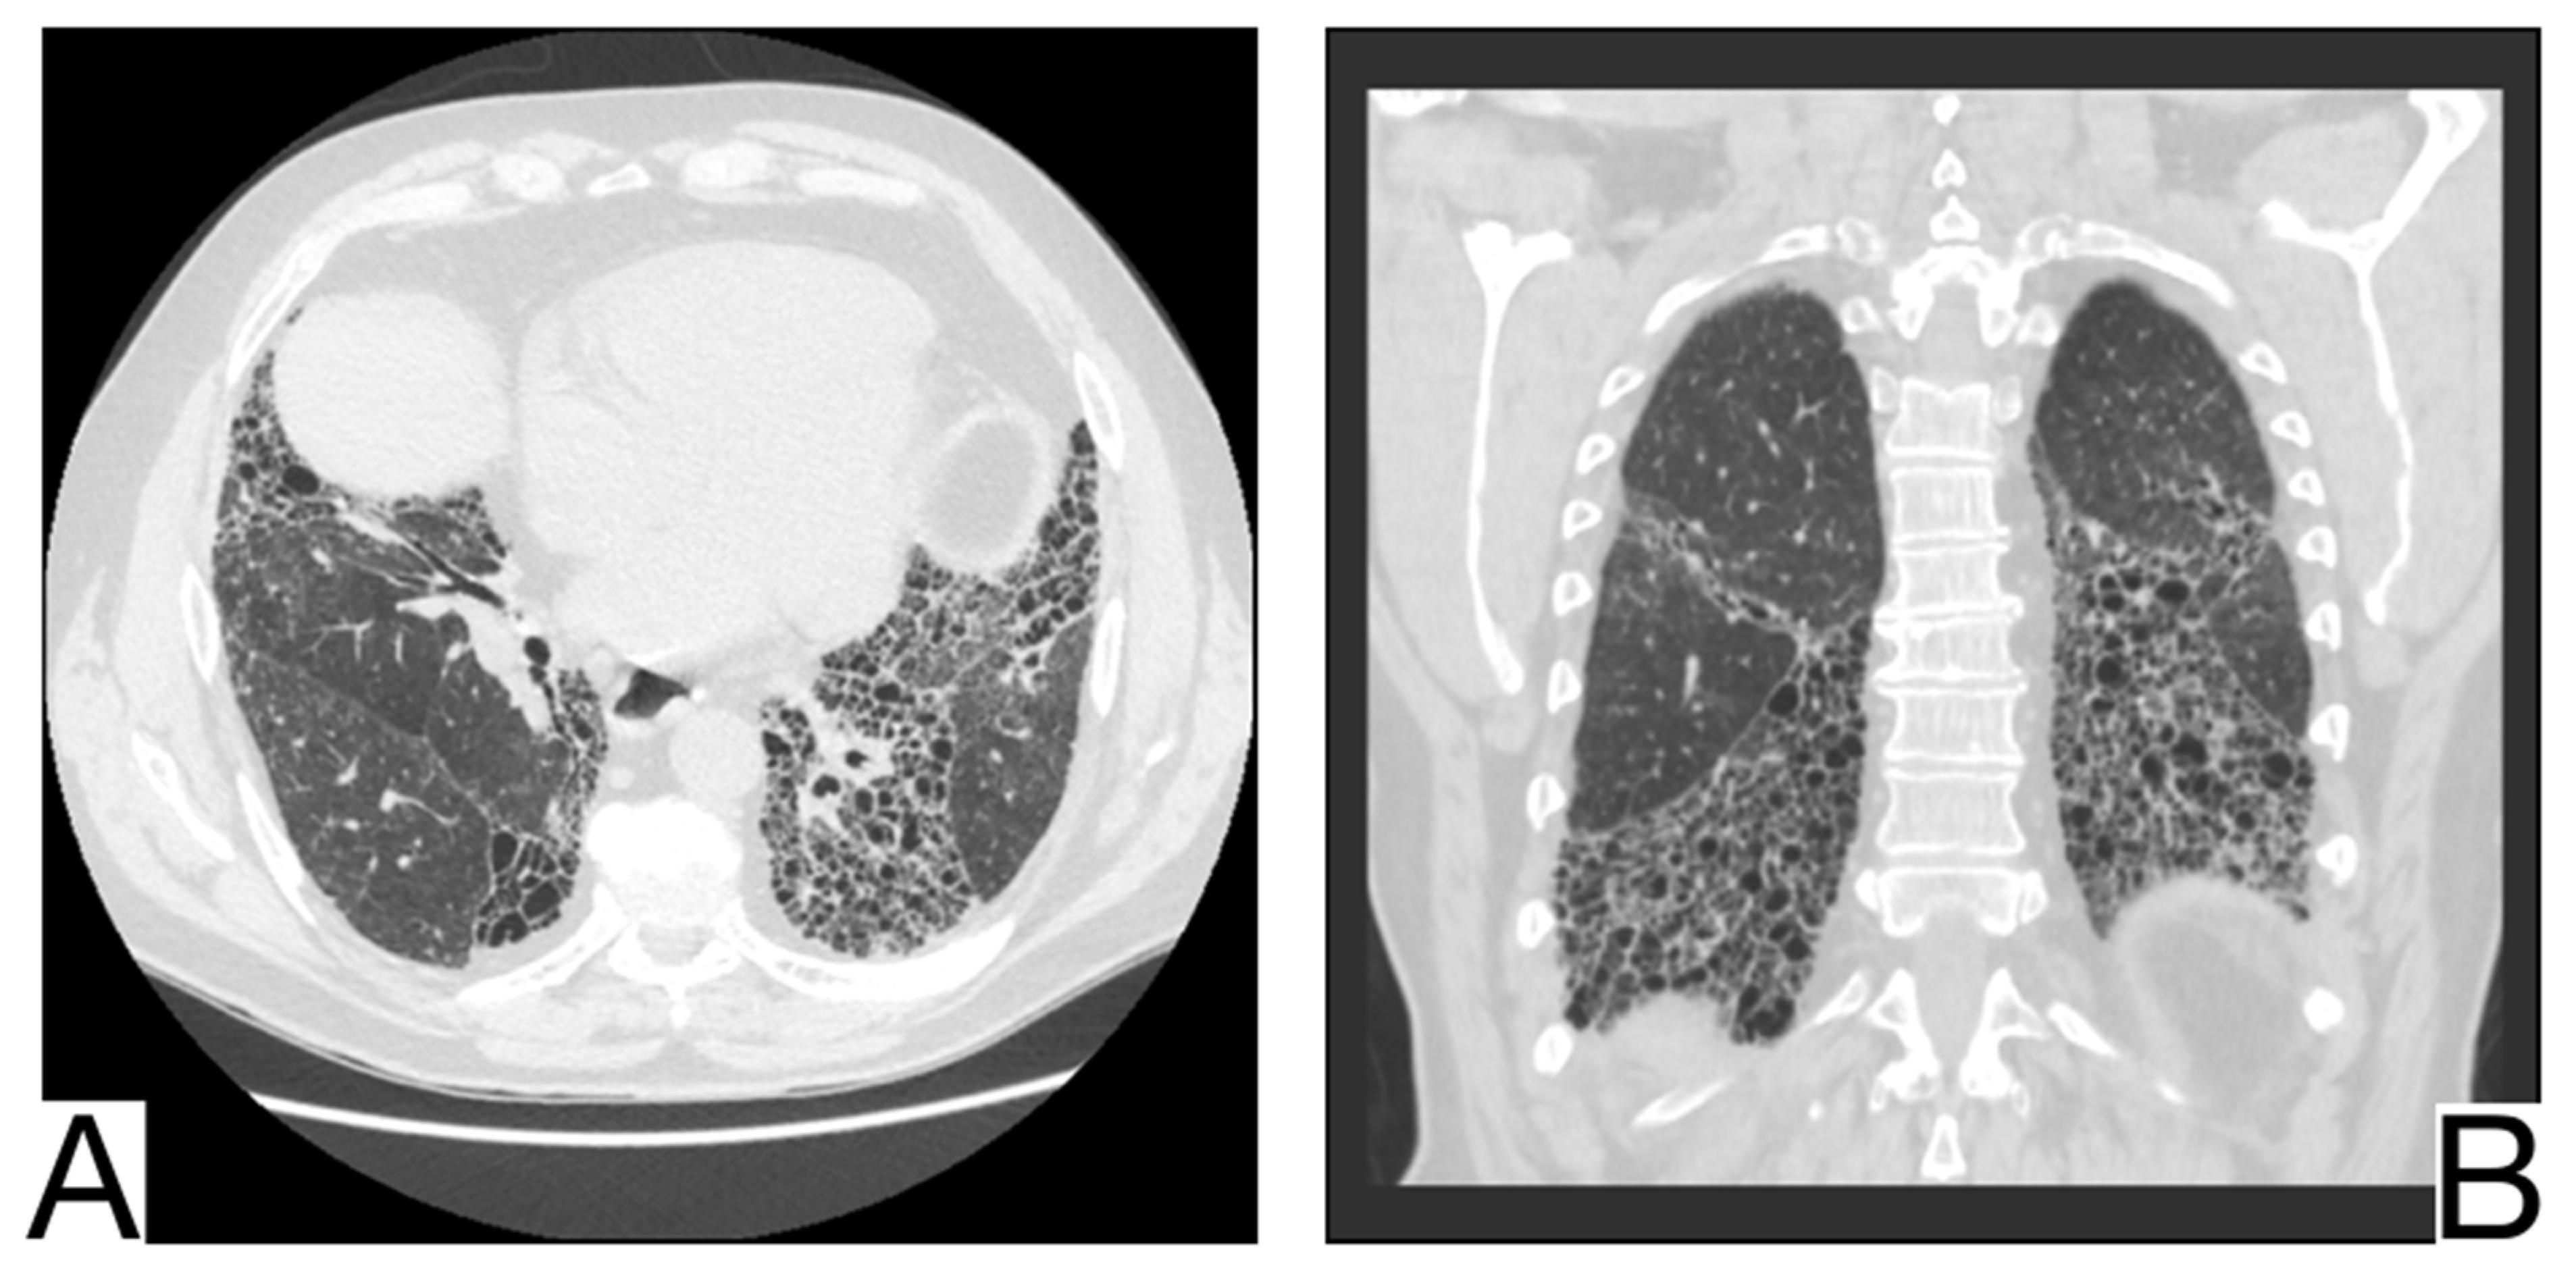

Pulmonary alveolar proteinosis-PAP is a syndrome caused by an accumulation of surfactant in the pulmonary alveoli. It can be primary in most cases or secondary to toxic inhalation syndromes, hematological neoplasms, and immune deficiency. History, laboratory tests, and comparison with previous HRCT are helpful [,].

CT differential diagnosis is highlighted by (Figure 12A,B): mainly centro-parenchymal and perihilar cobblestone areas; the juxtaposition of severely affected secondary lobules and normal secondary lobules [,]; rarely, condensations with air bronchogram in severe forms; progressive fibrotic changes; pleural effusions, cardiomegaly, and lymphadenopathy, which are characteristics of complicated PAP [].

Figure 12. Pulmonary alveolar proteinosis (A,B). Bilateral areas of crazy paving. Note. Case courtesy of Dr. Adrià Roset Altadill, Radiopaedia.org, rID: 74896.